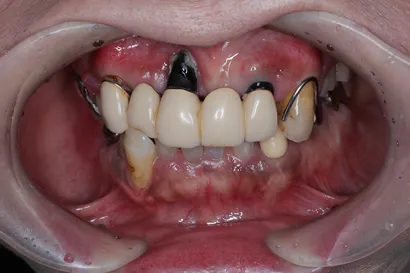

重度虫歯からの全顎インプラント治療

70代 男性

執刀医 Dr.大杉 治療内容 虫歯・歯周病が原因で噛み合わせが崩壊していたので、全顎的なインプラント治療を行い、口腔機能の回復を行いました。

上顎:ピンクポーセレンを用いたフルジルコニアインプラントブリッジ

下顎:奥歯=ジルコニアインプラントブリッジ、前歯=ジルコニアクラウン治療期間 1年6ヶ月 費用 上顎:420万 税抜

下顎:330万 税抜リスク セラミックのすり減りを防ぐために、ナイトガードを作成しています。毎晩使用することで、セラミックを長持ちさせることができます。 -